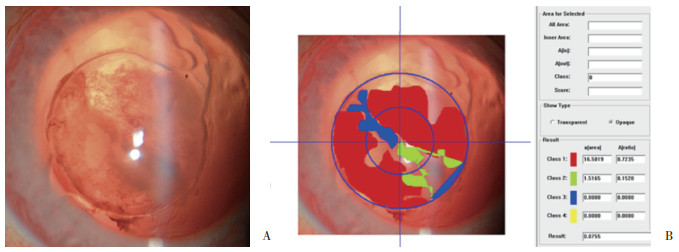

A组于术后14 d开始出现后囊膜混浊,见图 1、图 2。B组于术后7 d开始出现后囊膜混浊,见图 3。随着时间延长,2组后囊膜混浊程度逐渐加重。术后7 d、14 d、28 d A组平均后囊膜混浊评分小于B组,差异有统计学意义(P < 0.05),见表 2。

| 图 2 A组术后28 d裂隙灯检查晶状体后囊膜图像(A)及对应PCO-CAAS图像定量分析系统后囊膜混浊评分(B) × 16 Fig.2 Posterior capsular image (A) observed by slit lamp inspection and corresponding posterior capsular opacity score measured by PCO-CAAS (B) in group A at 28 days after surgery × 16 |

囊膜生物相容性是指残留于晶状体囊膜的晶状体上皮细胞对IOL的创面愈合反应,常用后囊膜混浊程度作为评价指标[1]。本研究中,A组IOL后表面经紫外线/臭氧处理,增加了其黏附性[13],与后囊膜贴合紧密,可使已居于中间的晶状体上皮细胞因缺少营养和机械性压迫而死亡,亦阻碍了晶状体上皮细胞从赤道部向后囊膜中央区迁移,故后囊膜混浊出现时间晚、程度轻,囊膜生物相容性较好。B组后囊膜混浊出现时间早,程度重,与LEE等[14]的研究结果一致。XU等[15]发现固定于IOL表面的亲水性聚乙二醇对晶状体上皮细胞的黏附作用小,可有效预防后发性白内障的发生,与本研究结果相反。LIN等[16]的体外细胞黏附实验结果显示,聚乙二醇处理的IOL不易黏附细胞、蛋白质等,考虑是由于聚乙二醇分子长链有一定的排斥体积,能够将蛋白质、细胞等生物大分子物质推出其排斥体积之外,远离材料表面。因此,聚乙二醇在排斥晶状体上皮细胞黏附的同时,也排斥蛋白质的黏附,导致IOL后表面与以胶原蛋白为主要组成成分的晶状体后囊膜之间留有间隙,易于形成晶状体上皮细胞迁移通道,使晶状体上皮细胞得以沿后囊膜表面增殖并迁移,发展为后囊膜混浊。本研究中,术后28 d常规HE染色也从组织病理学角度证实了这一结果。后囊膜混浊的发生是多因素综合作用的病理生理过程,生物组织与材料相互影响时程较长,影响因素较多,由晶状体上皮细胞合成的胶原蛋白、房水中的炎性细胞因子及虹膜睫状体中的色素上皮细胞等共同参与,现有技术手段还不能完全阻止其发生、发展,还需要进一步长期的研究,以寻找安全有效的方法预防后囊膜混浊。